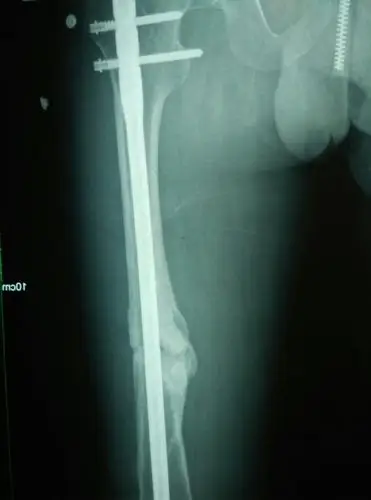

大腿骨折100天检查有少量骨痂.还会不会骨不连?

术后6个月见少量骨痂

大腿股骨骨折,现在手术两个月了,大家帮我看一下有没有骨痂生长?

骨骨干骨折术后3个月骨折线模糊骨痂少.